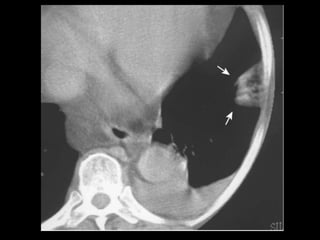

Hérnia de Morgagni